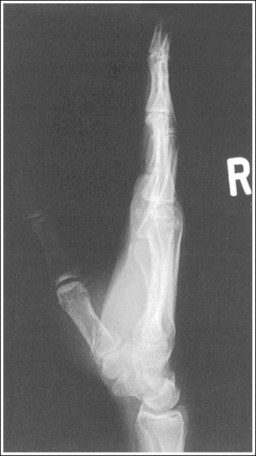

See Figure 4-10 and Box 4-4.

The digit of interest is in a lateral projection. The anterior aspect of the middle and proximal phalanges demonstrates midshaft concavity, and the posterior aspects of the phalanges show slight convexity.

• A lateral finger projection is accomplished by rotating the affected finger 90 degrees from the PA projection (Figure 4-11). Whether the hand is rotated internally or externally to obtain this goal depends on which direction will bring the finger closer to the IR. Typically, when the second and third fingers are imaged, the hand is rotated internally and, when the fourth and fifth fingers are imaged, the hand is rotated externally.

• Distinguishing lateral projection from rotated projection. To understand the difference between a truly lateral digit projection and a lateral projection that is rotated, study a finger skeleton in lateral and PA and AP oblique projections. Note how the midshaft concavity of the middle and proximal phalanges varies as the digit is rotated. In a lateral projection, the anterior aspect of these phalanges is concave, but the posterior aspect demonstrates slight convexity. In PA and AP oblique projections, both sides of the middle and proximal phalangeal midshafts demonstrate concavity, but the side toward which the anterior surface is rotated demonstrates a greater degree of concavity than the side toward which the posterior surface is rotated. The soft tissue width at either side of the phalanx also changes in the lateral and PA and AP oblique projections. More soft tissue is present on the side of the phalanges toward which the anterior surface is rotated (see Image 7).

Image 7

No soft tissue overlap from adjacent digits is present.

• Flex the unaffected fingers into a tight fist, allowing the finger of interest to remain extended. To visualize the proximal phalanx, it may be necessary to extend the affected finger with an immobilization device or to tape the unaffected fingers away from the affected finger. If the unaffected fingers are not drawn away from the proximal phalanx of the affected finger, they will be superimposed on the area, preventing adequate visualization (see Image 8). An immobilization device should not be used to extend the finger if a fracture is suspected and the device causes stress to the fractured area (see Image 9).

Image 8

Image 9

The IP joints are visible as open spaces, and the phalanges are not foreshortened.

• The IP joints are open, and the phalanges are demonstrated without foreshortening as long as the finger was positioned parallel with the IR and the central ray was perpendicular to and centered with the PIP joint.

• When the third and fourth digits are imaged, they are positioned at a greater OID than the second and fifth digits. To keep the third and fourth digits parallel with the IR, it may be necessary to place an immobilization device beneath their distal phalanges. When a finger is not positioned parallel with the IR and perpendicular to the central ray, the IP joint spaces are closed and the phalanges are foreshortened.

The PIP joint is at the center of the exposure field. The distal, middle, and proximal phalanges and the metacarpal head of the affected digit are included within the collimated field.

• Center a perpendicular central ray to the PIP joint to place it in the center of the image. Open the longitudinal collimation to include the distal phalanx and the metacarpal head. Transversely collimate to within 0.5 inch (1.25 cm) of the finger skin line.

• One third of an 8- × 10-inch (18- × 24-cm) detailed screen-film or computed radiography IR placed crosswise should be adequate to include all the required anatomic structures.

Concavity is demonstrated on both sides of the middle and proximal phalangeal midshafts, indicating that the finger was not adequately rotated for this image.

The unaffected fingers were not flexed enough to prevent soft tissue or bony superimposition of the affected digit's proximal phalanx.

Tightly flex the unaffected fingers away from the affected finger. Hyperextending the affected finger with an immobilization prop may also help increase demonstration of the proximal phalanx if a fracture of this area is not suspected.